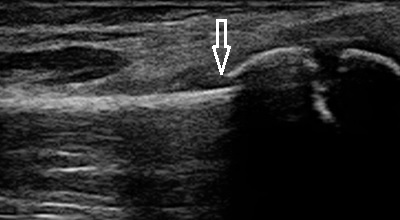

左手首 超音波画像

川越市 小学5年生男子。 サッカークラブチーム所属。 左手関節の痛み、 橈骨遠位部の骨折。

翌日に当院に来院した時に小学生は「少しだけ痛い」と言うように手首は動かせました。超音波検査では

左橈骨の遠位部が背側に転移して骨折している様子が認められました(画像矢印)。

小学生の左の手首は見た目に腫れも認められず、痛みも強くなかったので付添いの母親は骨折が

あった事にビックリしていました。

この小学生のように超音波検査をしていなかったら、骨折を見逃していたかも知れません。当院では、

転んだり、ぶつけたり、関節を捻ったりした時には、必ず超音波検査を実施して患部の状態を客観的に

評価しています。ケガをして痛みが軽減していない方は、今すぐ当院までご連絡ください。